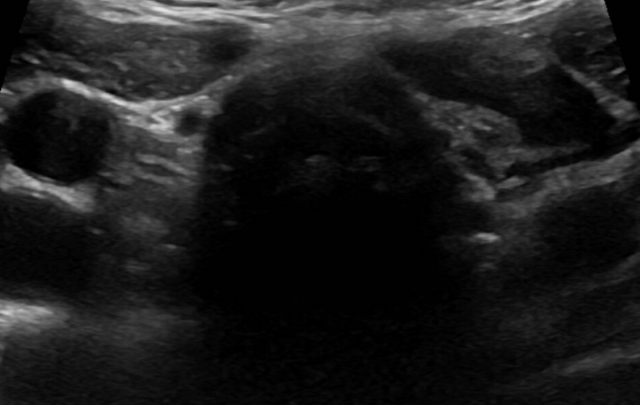

Differentiated thyroid cancer (DTC) includes papillary thyroid cancer (PTC) and follicular thyroid cancer (FTC). PTC is the most common form ...